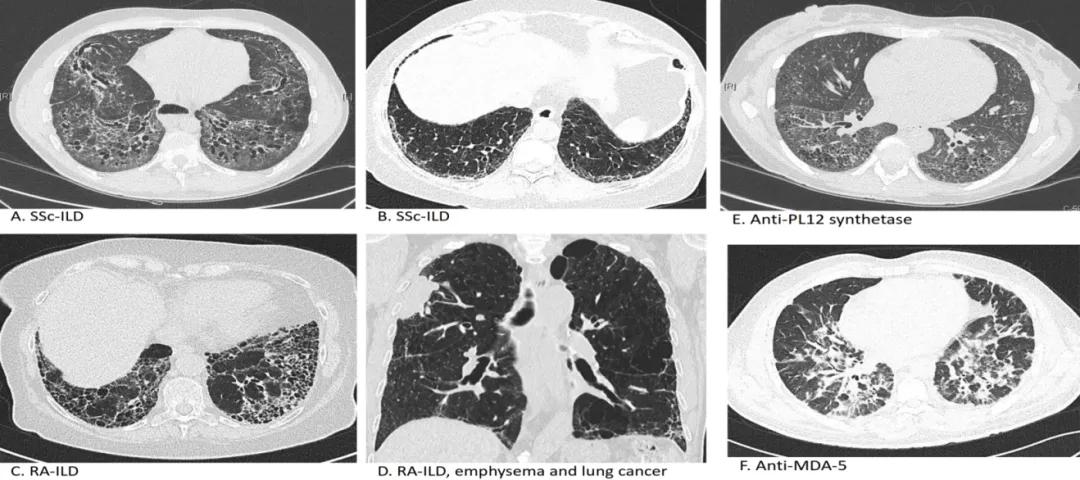

纤维化性ILD的HRCT表现 [24] :

(来源:Wijsenbeek M, Cottin V. Spectrum of fibrotic lung diseases. N Engl J Med 2020;383:958-68.)

这些影像是系统性硬化症、抗合成酶综合征、类风湿关节炎引起等不同类型疾病导致纤维化的HRCT表现。